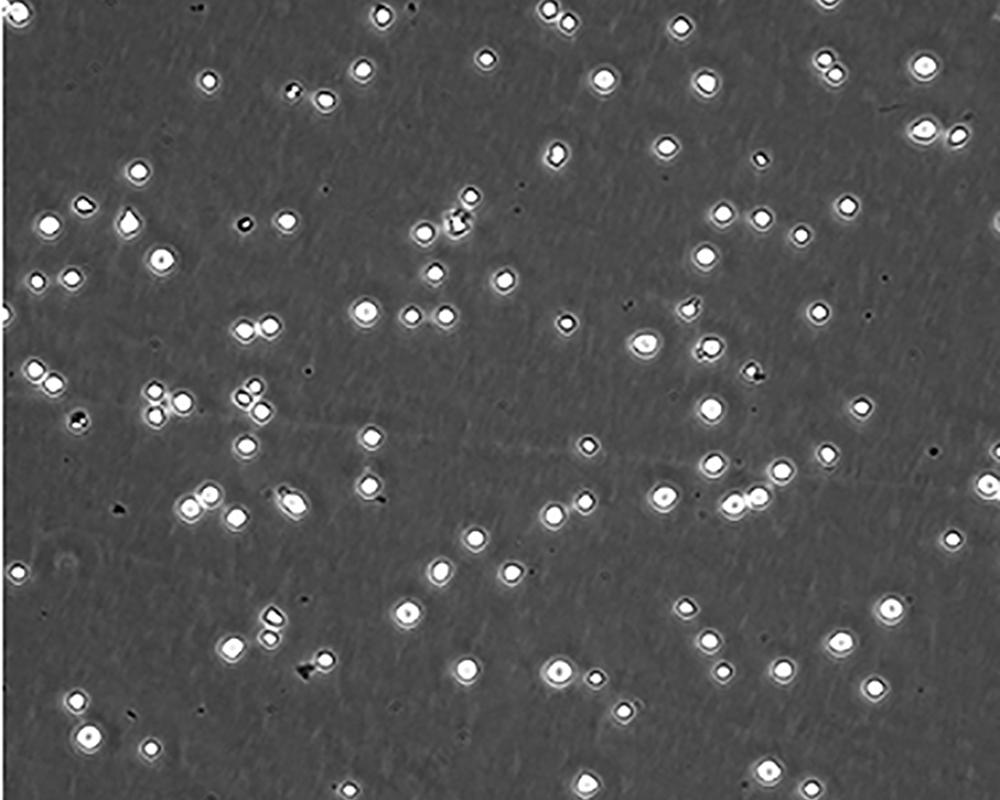

中文名稱 人急性淋巴細(xì)胞白血病細(xì)胞

組織來源 急性T淋巴細(xì)胞白血?。慌?/td>

生長特性 suspension

形態(tài)特征 lymphoblast

細(xì)胞描述 CEM/C1是人T細(xì)胞白血病細(xì)胞株CCRF-CEM(見ATCC CCL-119)具有喜樹堿抗性的衍生株。1991年細(xì)胞株選擇并亞克隆了對CPT的抗性。細(xì)胞表現(xiàn)出對CPT類似物水溶性的托泊替康和非水溶性的9-氨基-CPT及10,11-亞甲二氧基-CPT具有交叉抗性。CEM/C1細(xì)胞對CPT的敏感性較母系CEM細(xì)胞低31倍。CEM/C1細(xì)胞表現(xiàn)非典型的多藥抗性和轉(zhuǎn)換拓補(bǔ)異構(gòu)酶I催化活性。對CPT的抗性維持6個(gè)月以上。